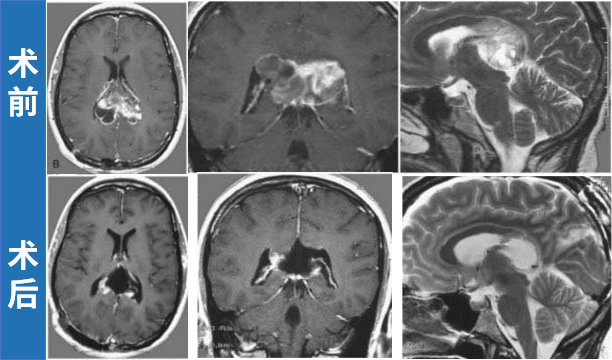

33岁孕妇Olive在孕期出现严重头痛、行走不稳及轻度记忆减退症状。检查发现双侧侧脑室存在巨大肿瘤,并合并脑积水症状。考虑到患者情况,立即进行囊液引流和肿瘤活检以降低颅内压。活检结果显示为毛细胞型星形细胞瘤,Olive症状迅速缓解,妊娠期间无需进一步治疗。

MRI影像学表现:轴位(左上、左下)、冠状位(右上)和矢状位(右下)序列显示一个大型囊性肿瘤占据双侧侧脑室后部。尽管肿瘤体积巨大,但Olive最终顺利分娩。后续由INC巴特朗菲教授实施手术,肿瘤被完全切除,同时保留双侧胼胝体结构。术后患者出现轻度记忆减退,持续数周后缓解;未出现任何神经或认知功能缺损。随访MRI显示肿瘤无复发征象。